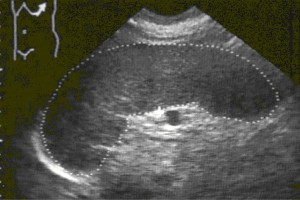

Diplomados en Ultrasonografía